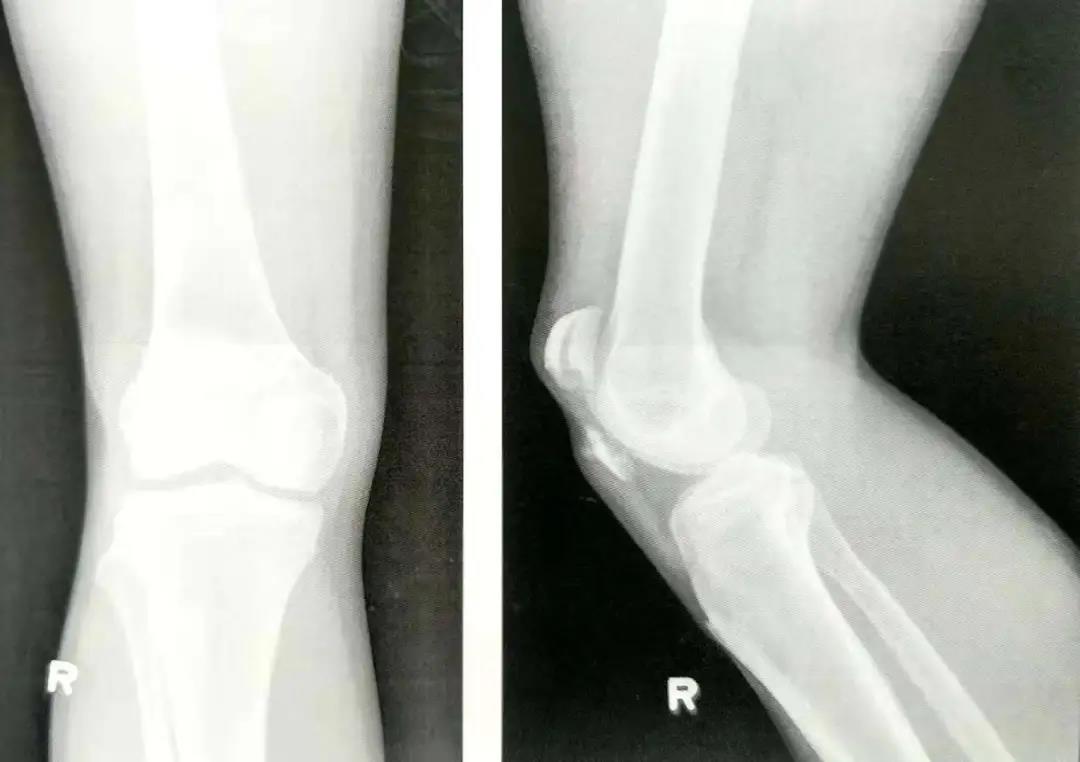

髌骨骨折手术技巧!

- 外科手术的目的是为了获得解剖复位,并在骨折愈合前以内固定的方式来维持复位状态,恢复髌骨骨折后的伸肌装置。

- 前张力带可将股四头肌产生的牵拉力转化为对关节面的压力。